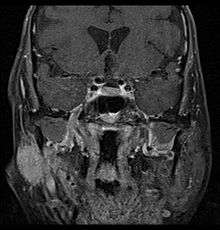

![]() Coronal MRI showing right parotid adenoid cystic carcinoma with perineural spread of tumor. The tumor originates in the right parotid gland and spreads along the trigeminal nerve via the auricuotemporal branch extending intracranially through the foramen ovale at the skull base towards Meckel's cave |